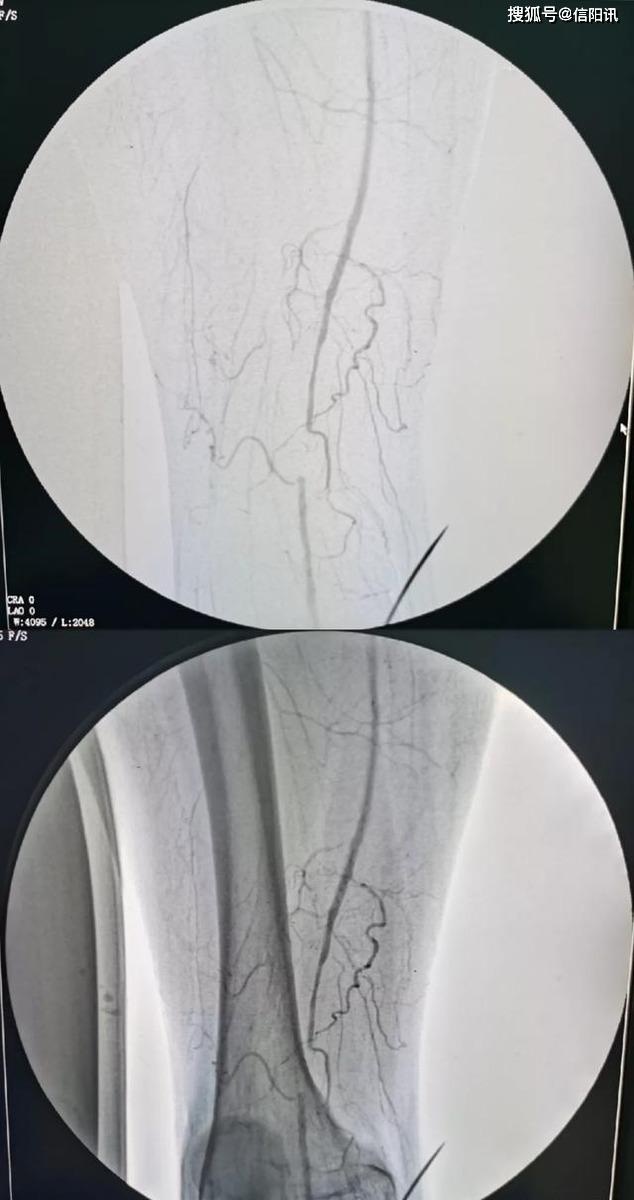

脑动脉狭窄后球囊扩张支架置入术后造影见血管恢复原来的大小通畅无阻

下肢动脉硬化闭塞症下肢动脉球囊扩张支架成形介入手段

我院成功开展首例dsa下经皮下肢动脉造影球囊扩张成形支架置入术

罗山县人民医院下肢动脉闭塞介入技术新进展——药物涂层球囊扩张术

左下肢动脉硬化患者

明确病变的性质,范围,程度,然后通过球囊扩张,或者置入动脉支架,开通